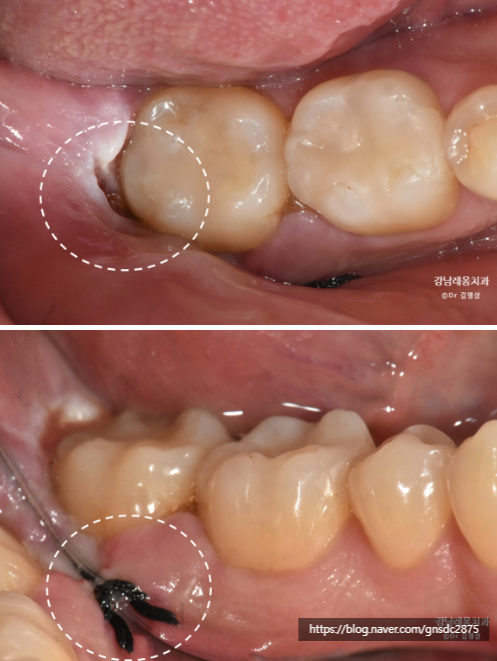

타치과에서 사랑니 발치를 하다 신경관이 가까워

뿌리를 남긴 채로 마무리하신 분입니다.

표시한 곳에 뿌리가

신경관가 가깝게 위치하여 남아있는 것이 보입니다.

발치 한달 후 발치부위의 불편감이 들어

남은 뿌리의 발치를 원해

강남레옹치과에 방문해주셨습니다.

CT상으로도 남은 뿌리가

신경관과 매우 근접해 보여

거리를 정확하게 파악하여

조심스럽게 발치하기로 하였습니다.

다행히 뿌리를 모두 잘 발치하였고

발치 후 엑스레이 촬영을 통해

남은 조각이 또 있지 않은지 확인하였습니다.

정확한 계획대로 발치를 진행했으나

추후 신경손상 증상이 없는지

일주일 동안 체크를 할 필요가 있습니다.

일주일 후 회복이 잘 되었고

신경손상없이 모두 정상이었습니다.